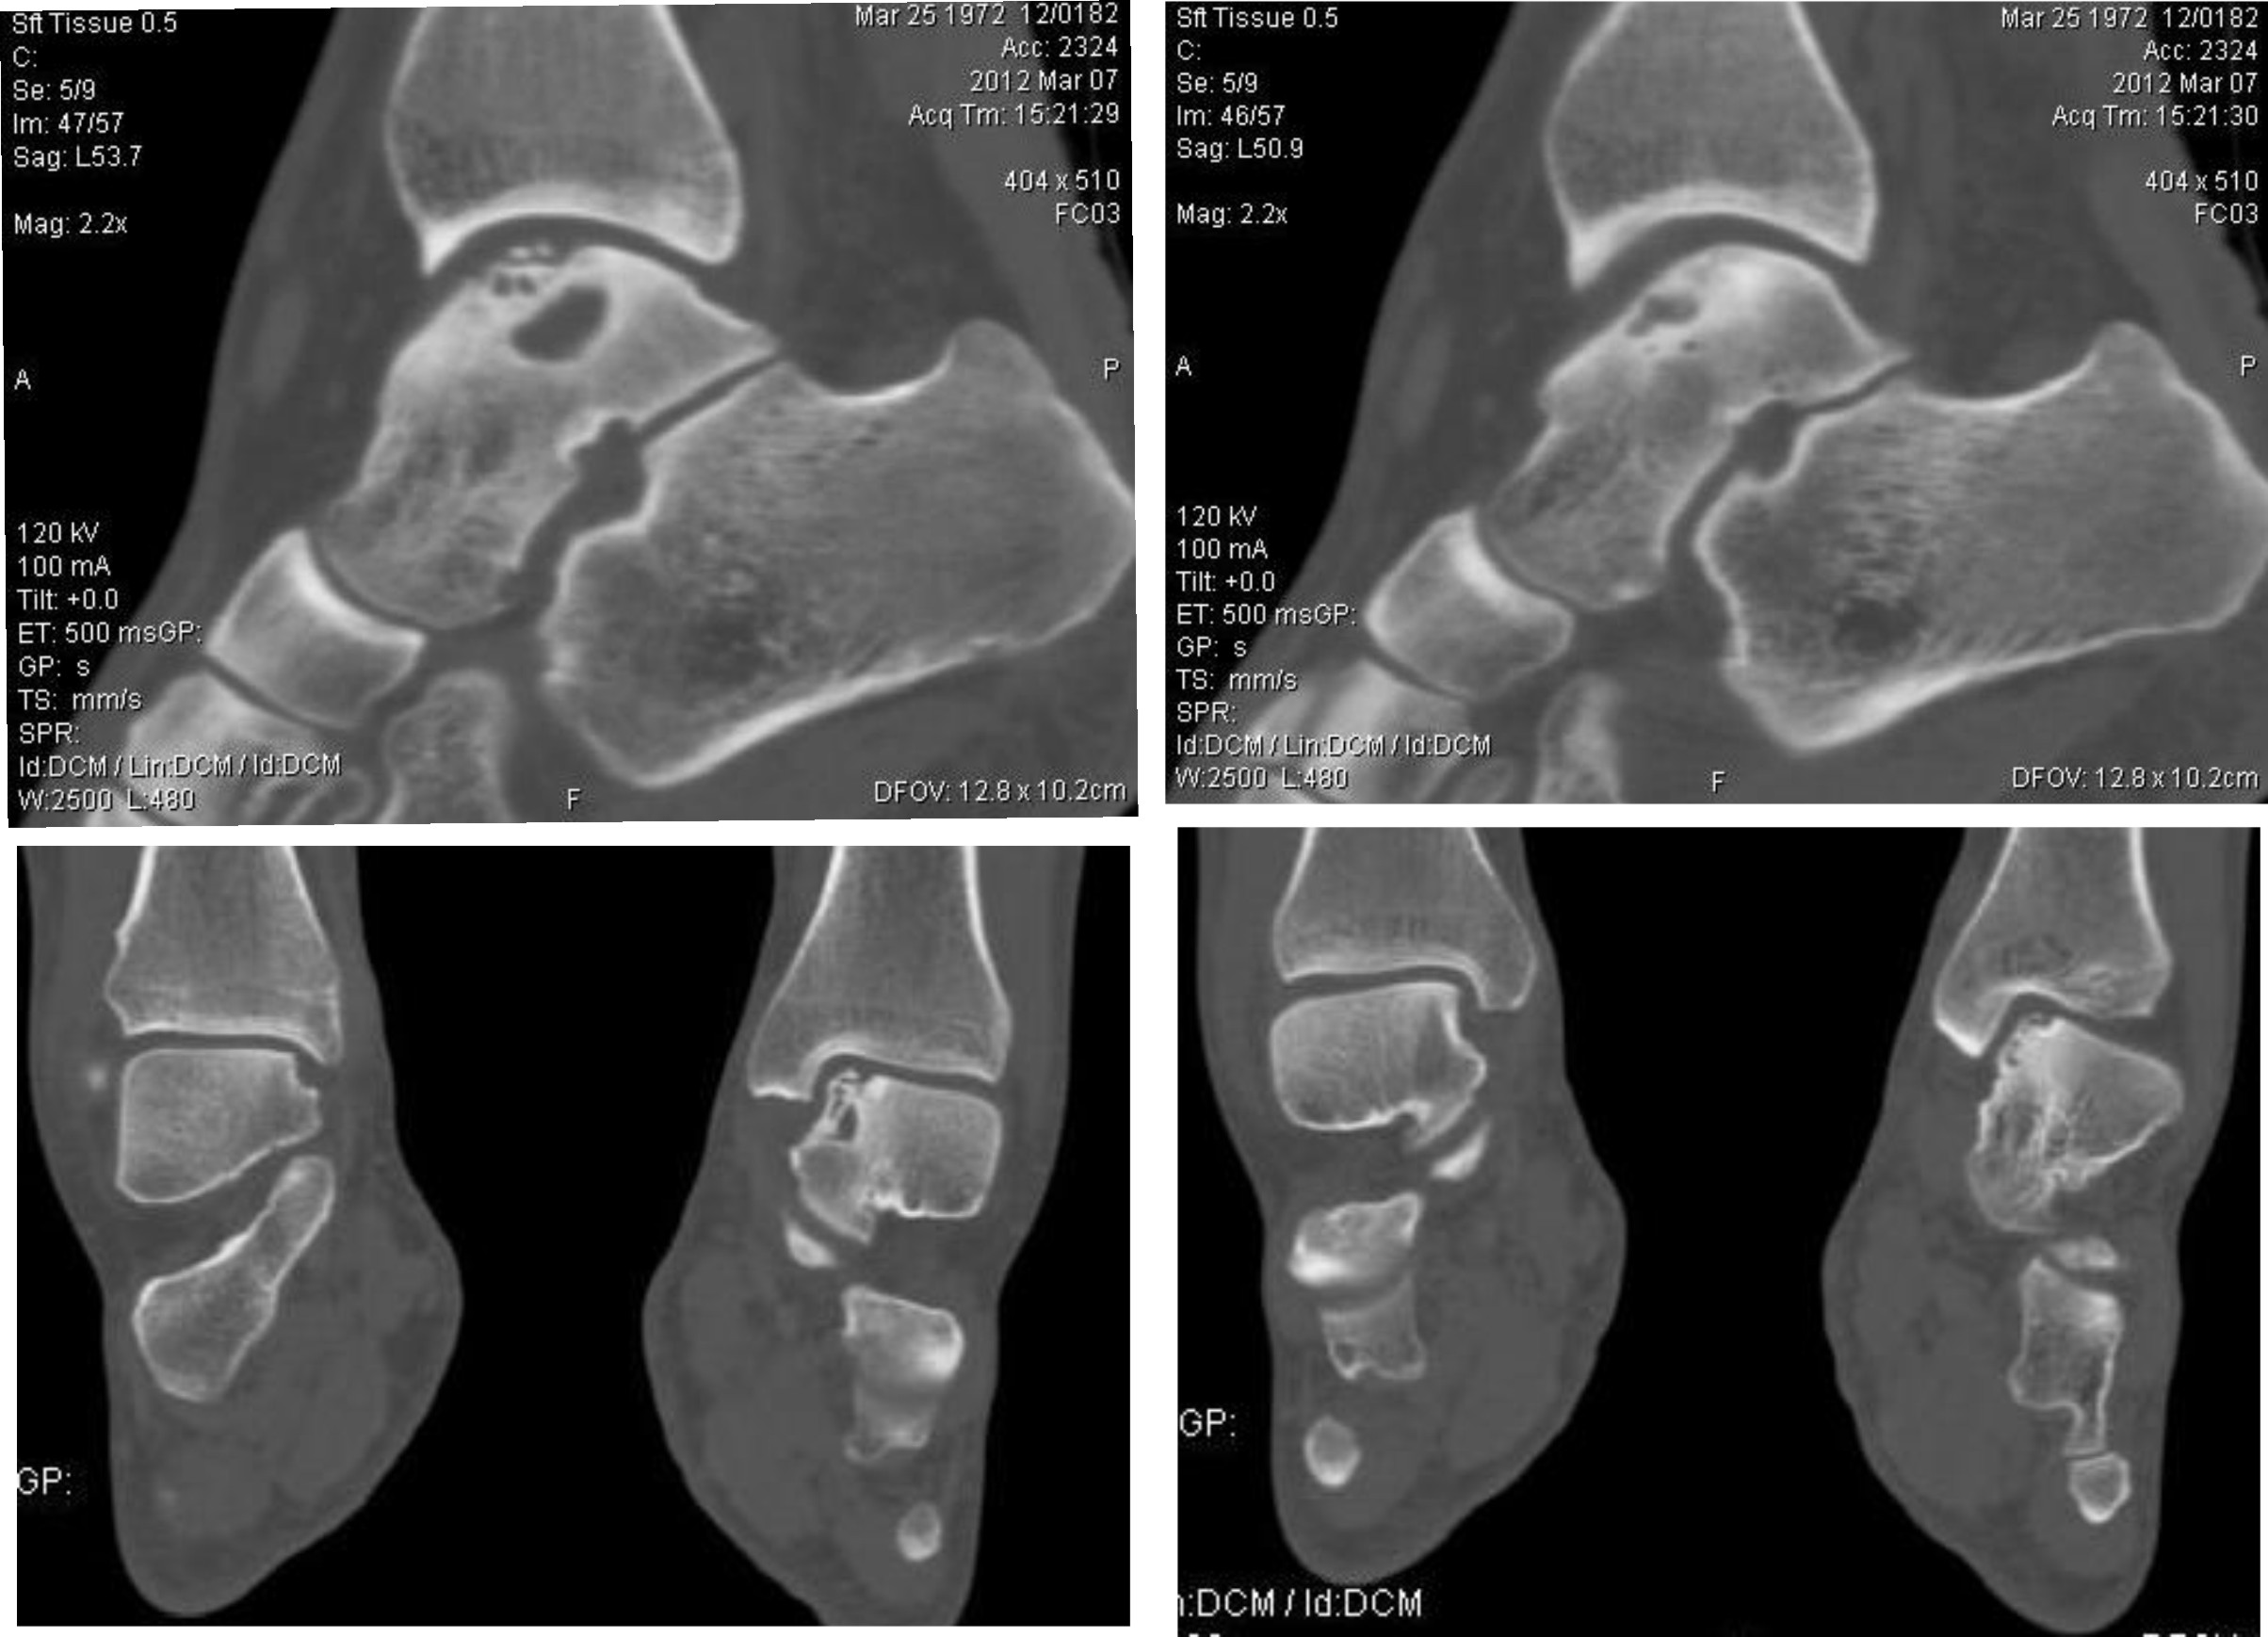

[Ortho] Аваскулярный некроз таранной кости

Пациентка 40 лет, в течение последних 8-9 мес. беспокоила боль в левом голеностопном суставе

после значительной физической нагрузки (по роду деятельности вынуждена проходить в день не

менее 15 км). Факт травмы отрицает. Лечилась самостоятельно, мазями и приемом НПВП. В

последнее время боль стала возникать после умеренной нагрузки, присоединились отек и

хромота. Прием НПВП и ограничение нагрузки до уровня бытовой болевой и отечный синдром

купируют. Обратилась к нам, выявлены изменения таранной и пяточной кости, представленные

на КТ. Вопрос: единственным ли выходом является артродез или можно обойтись менее

радикальным вмешательством? Смущает невыраженная клиника и молодой возраст пациентки...